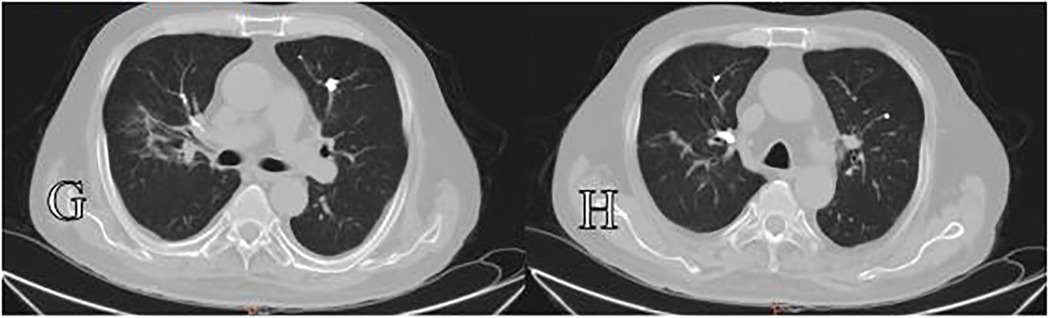

A 69-year-old woman was admitted to our hospital due to refractory back pain for approximately one month. Preoperative evaluation revealed that the patient had a bone mineral density T-score of −3.2 at L1-L4, indicating severe osteoporosis, imaging findings from MRI showing fresh osteoporotic vertebral compression fractures at L1 and L2 (characterized by T1-weighted hypointensity and T2-weighted hyperintensity with edema), while lower extremity Doppler ultrasound detected no pre-existing venous thrombosis. The routine preoperative medical evaluation was normal. Given her symptoms and spine images, she was treated with percutaneous vertebroplasty under local anesthesia (1% lidocaine) with continuous monitoring of heart rate, blood pressure, and oxygen saturation. Bone cement was typically infused into the vertebral body using a unilateral transpedicular approach, with intermittent anteroposterior and lateral fluoroscopy guidance. The percutaneous vertebroplasty procedure for L2 was completed successfully and approximately 4.5 ml of bone cement was infused (polymethylmethacrylate, viscosity: high, mixed for 3 min before injection). Then, the percutaneous vertebroplasty procedure for L1 was performed as follows. When the injection volume reached approximately 1.5 ml, anterior cement leakage in the paravertebral venous system was detected on lateral fluoroscopy. Immediately, vital signs were observed to be continuing smoothly with no obvious fluctuations (HR 72 bpm, BP 135/85 mmHg, SpO2 99%). Additionally, there were no complaints of cardiorespiratory discomfort by the patient. As the vertebral fill was inadequate, we continued the bone cement injection procedure. However, the trajectory tracking of cement leakage in the paravertebral venous system was gradually prolonged with continuous additional cement injection (Figure 1). When the cement injection dose reached approximately 4 ml, cement disk space extravasation was detected and we terminated the procedure at that time. The postoperative outcome was seemingly good and had no symptoms such as dyspnoea, coughing, haemoptysis, dizziness or palpitation. However, the postoperative thoracolumbar x-ray presented that multiple tubular and branching cement emboli were scattered throughout the lungs (Figure 2). Intraoperative lateral fluoroscopy data were analysed retrospectively, and we detected that sustained cement injection resulted in the migration of the distal part of the prolonged cement leakage tracks in the paravertebral venous system on the last lateral fluoroscopy. The subsequent treatment consisted of two days of conventional postoperative treatment and electrocardiogram monitoring, with no use of anticoagulation. The patient's vital signs continued smoothly until discharge. The patient was satisfied with the operation because her back pain was significantly relieved. With a one-year clinical follow-up after discharge, she remained asymptomatic. During the follow-up after discharge, it was noted that the patient developed pneumonia more than one year after leaving the hospital. Computed tomography (CT) at the local hospital confirmed the presence of bone cement emboli within the pulmonary artery branches, as illustrated in Figure 3, following successful treatment, the patient recovered uneventfully and was discharged from the hospital.

Figure 2. (D) Preoperative chest x-ray (E,F) postoperative thoracolumbar x-ray showing cement leakage into the paravertebral venous system and multiple cement emboli scattered throughout the lungs.